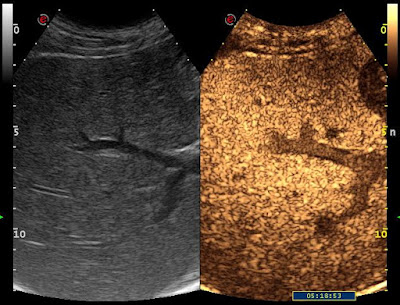

Májmetastasisok Szerző: admin | jún 23, 2011 | CEUS, Focal liver lesions | Nincsenek hozzászólások alapbetegség: pancreastumorUH-vizsgálattal egy góc sem volt egyértelműen elkülöníthető. 8028902011.06.21. – US